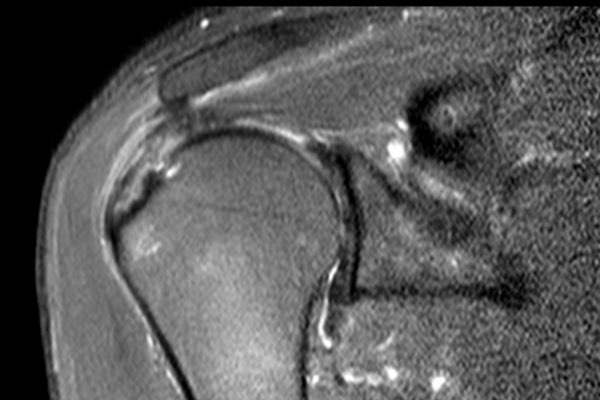

Nhấp vào hình ảnh để phóng to, sau đó cuộn qua các lát cắt.

Có hình ảnh rách toàn bộ chiều dày gân cơ trên gai kèm co rút và teo cơ.

Lưu ý các dải mỡ trong cơ tròn bé, cơ trên gai và cơ dưới gai.